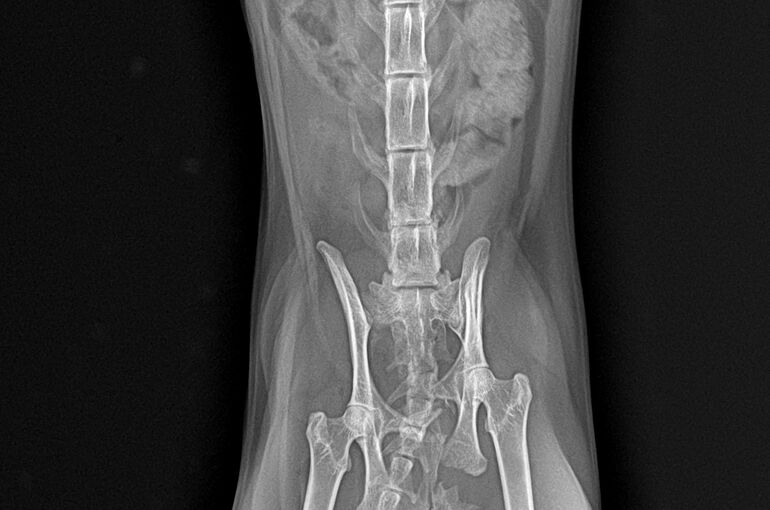

まずはレントゲンを撮りました。それが以下の写真です。

左側の骨盤(腸骨と座骨)が骨折しています。幸い仙腸関節は問題ないかと思われました。